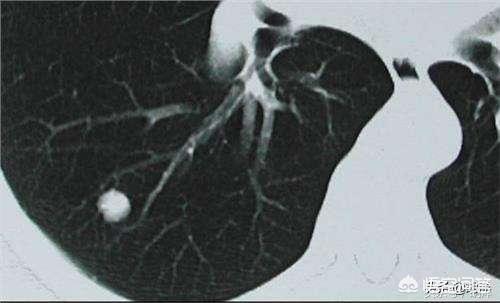

結節は固形結節とすりガラス結節に分類される。

肺結節はその密度によって種類分けされ、胸部CTで白い点として写る密度の高い結節は固結と呼ばれ、地中硝子結節は密度が薄くガラスに水蒸気が付着したように見える。地中ガラス結節、特に純粋な地中ガラス結節は悪性度が高い傾向がある。

一般に、肺にできる直径3cm以下の密度増加影を肺結節と呼びますが、その危険度は大きさだけでなく、結節の形態、密度、増殖速度も合わせて判断する必要があります。

一般に、直径8mm以上の結節は細心の注意が必要であり、特に、形が不規則であったり、あるいはバリ状のパターンを伴っていたり、実像と虚像が混在していたり、胸膜に隣接していたり、胸膜陥凹が出現していたりする場合は、悪性腫瘍の可能性を強く警戒する必要がある。必要に応じて穿刺生検や直接切除を行う。

8mm未満の結節、特に6mm未満の結節については、綿密な観察と検討が必要である。次のような状態のほとんどは良性である:結節の性質が短期間に著しく変化し、縁が滑らかになるかぼやけ、小葉化がない;結節の密度が均一か薄くなる;結節の密度が増加することなく縮小または消失する。